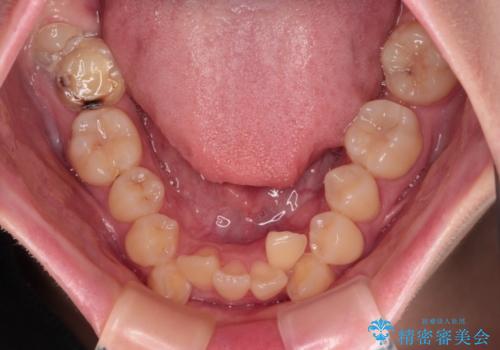

上下の八重歯とクロスバイト ワイヤー装置での抜歯矯正

- 八重歯とクロスバイトを気にして来院された患者様です。

上下ともに八重歯が顕著であり、前歯のクロスバイトがあったため、上下左右の第一小臼歯4本を抜歯し、ワイヤー装置での抜歯矯正を行うこととしました。